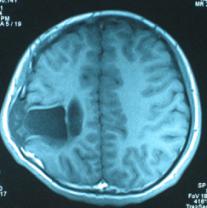

头颅CT和MRI可见颅骨缺损区下方软脑膜囊肿、脑软化灶或脑室穿通畸形(图2)。

图2:①和②CT及骨窗相显示右顶部颅骨缺损,其下方脑组织呈低密度改变;③-⑥MRI右顶局部颅骨缺如,脑组织轻度向外膨隆,右顶叶侧脑室体部旁局部脑组织缺如,代之以囊性长T1、长T2信号。